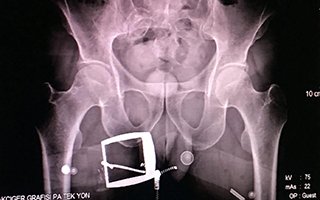

Makatına gizlediği uyuşturucuyu İstanbul'a götürmek isteyen İranlı kadın, Erzurum'da Polis ekiplerine yakalandı. Uyuşturucunun yeri, röntgen çekilerek bulundu.  Kaçakçılık ve Organize Suçlarla Mücadele (KOM) Şubesi ekipleri, uygulama sırasında durdurdukları bir yolcu otobüsünde arama yaptı. İranlı B.H.’ye ait olduğu belirlenen valizde, 21 parçadan oluşan ve ‘met’ olarak bilinen 607 gram ‘metamfetamin’ maddesi ele geçirildi. Gözaltına alınan B.H.’nin hareketlerinden şüphelenen narkotik polisi, kendisini sağlık kontrolü için hastaneye götürdüğünde röntgen çekilmesini de istedi. Röntgen filmi sonuçlarında İranlı kadının uyuşturucuyu kapsüller halinde makatına soktuğu anlaşıldı. Tıbbi müdahaleyle 4 kapsül halinde 96 gram ‘met’ ve bir kapsülde 28 gram reçine esrar çıkarılırken, uyuşturucunun piyasa değerinin 50 bin lira olduğu belirtildi. İranlı B.H. tutuklanarak cezaevine konuldu.  Emniyet, röntgen filmi ile birlikte ekle geçirilen uyuşturucu maddeleri basınla paylaştı.